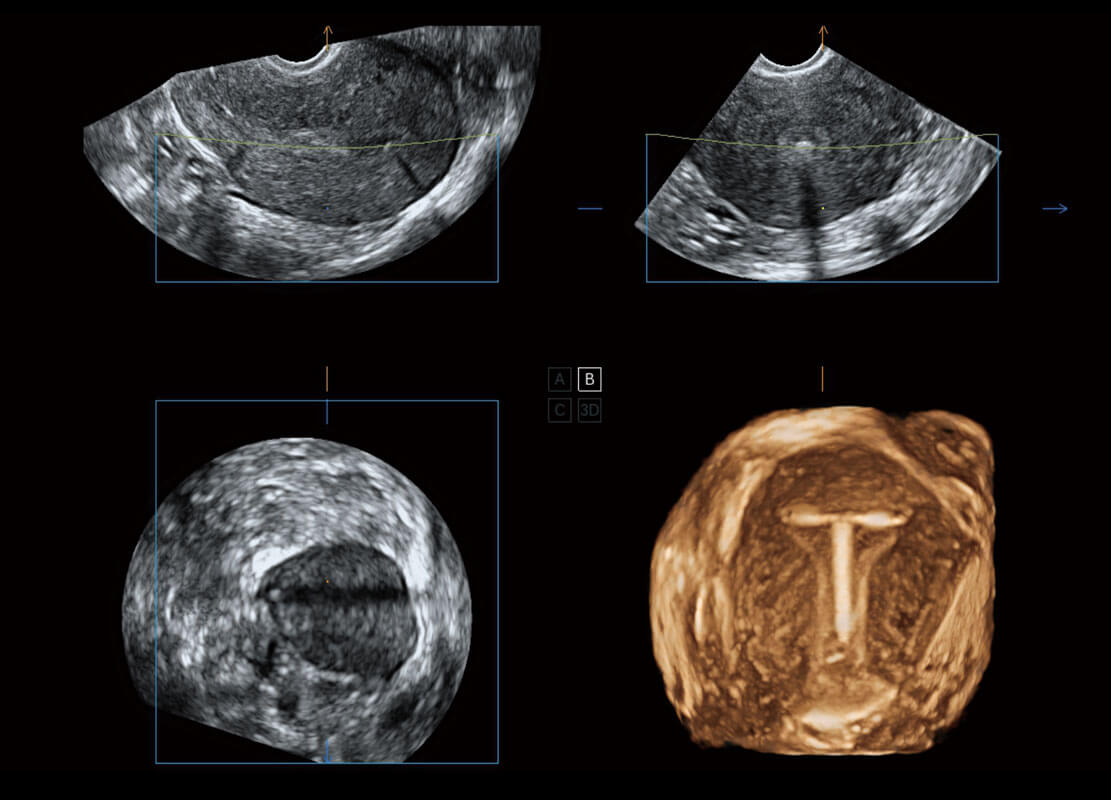

胎心筛查

P60搭载一系列胎儿心脏成像技术,实现精细的胎儿心脏评估。

• 四腔切面

• 四腔心血流

• 右室双出口

• 胎心容积成像